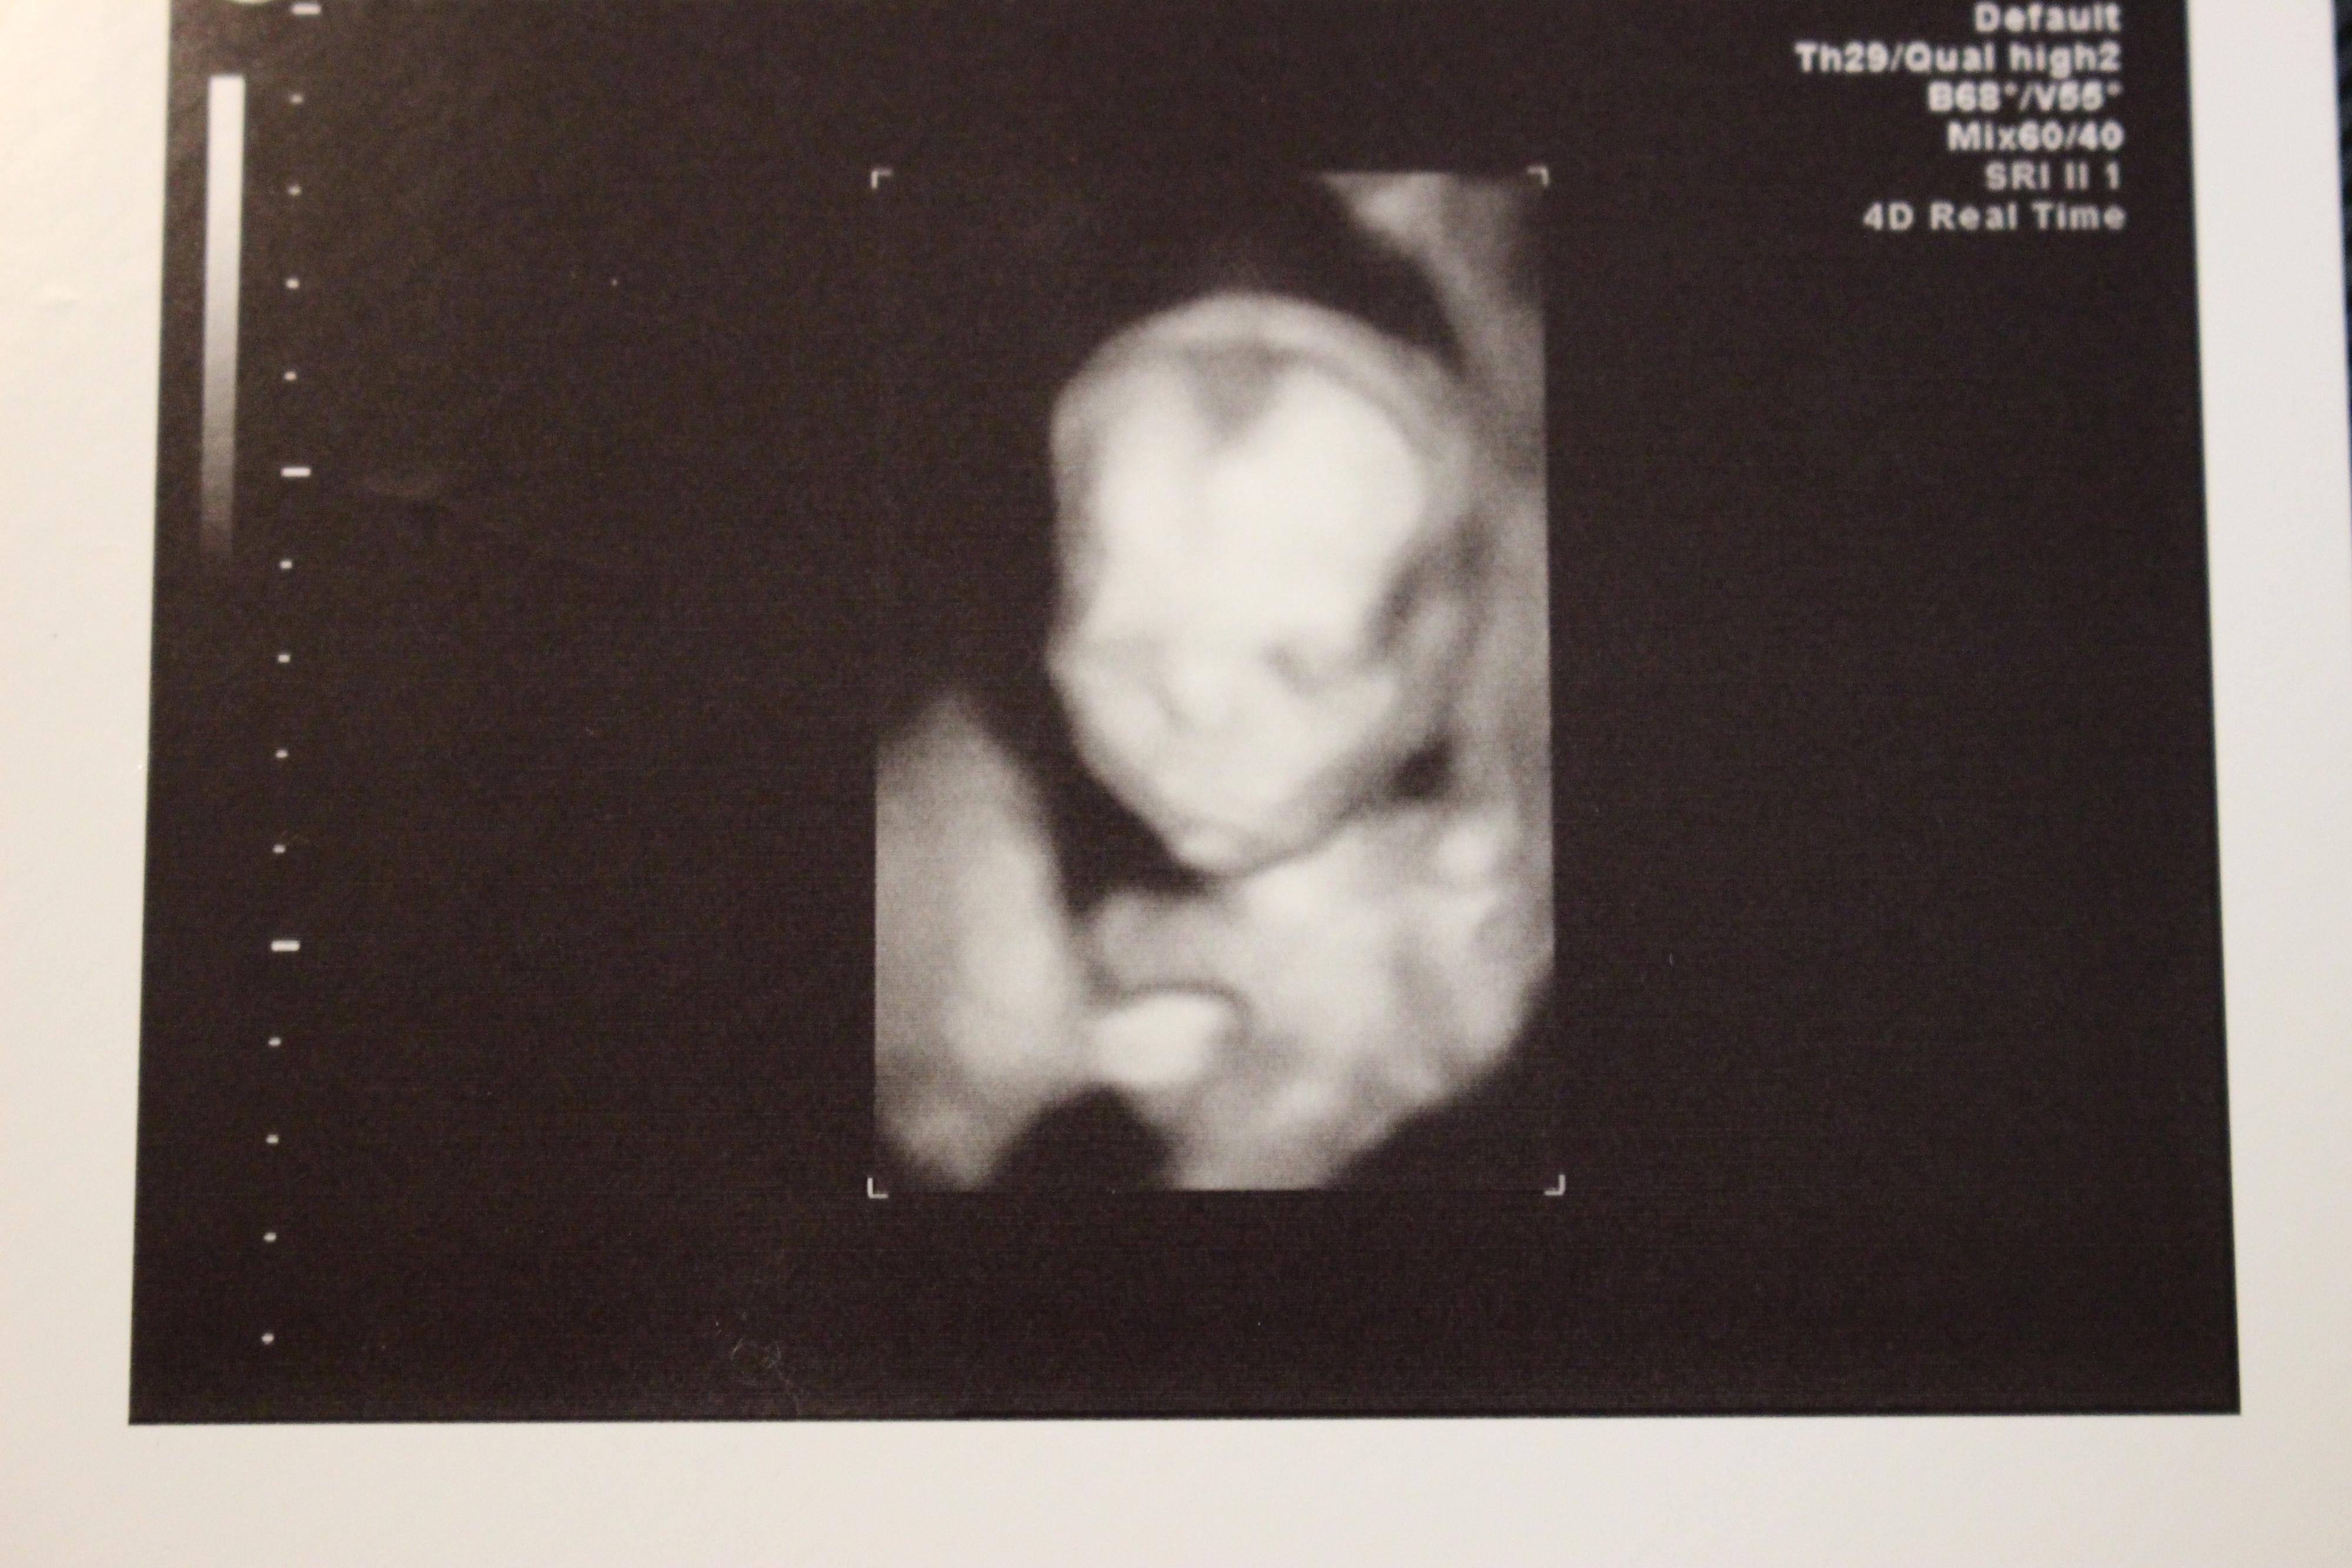

妊娠18週目の4Dエコー写真

4D画像になり目鼻立ちもはっきりと確認できます。赤ちゃんの胎動は”金魚を手のひらで包み込んでいる感じ”がしました。赤ちゃんの心臓に異常がないかを確認し、母体側では子宮筋腫が胎盤裏に位置しているので注意が必要だと説明されました。信頼のおける医師と出会い、その医師に全てを託す思いで分娩申込書を提出しました。